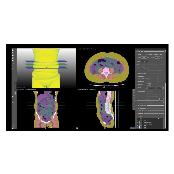

MEDIP PRO is a comprehensive software that processes medical images, enabling image analysis, 3-dimensional construction, modeling, and design with its automatic artificial intelligence (AI) segmentation technology at its core.

MEDIP PRO is equipped with One-Click Segmentation, which helps auto-segmentation

and extracts virtually all human body components in medical images (CT and MR) including patients’ organs and pathologic lesions.

and extracts virtually all human body components in medical images (CT and MR) including patients’ organs and pathologic lesions.